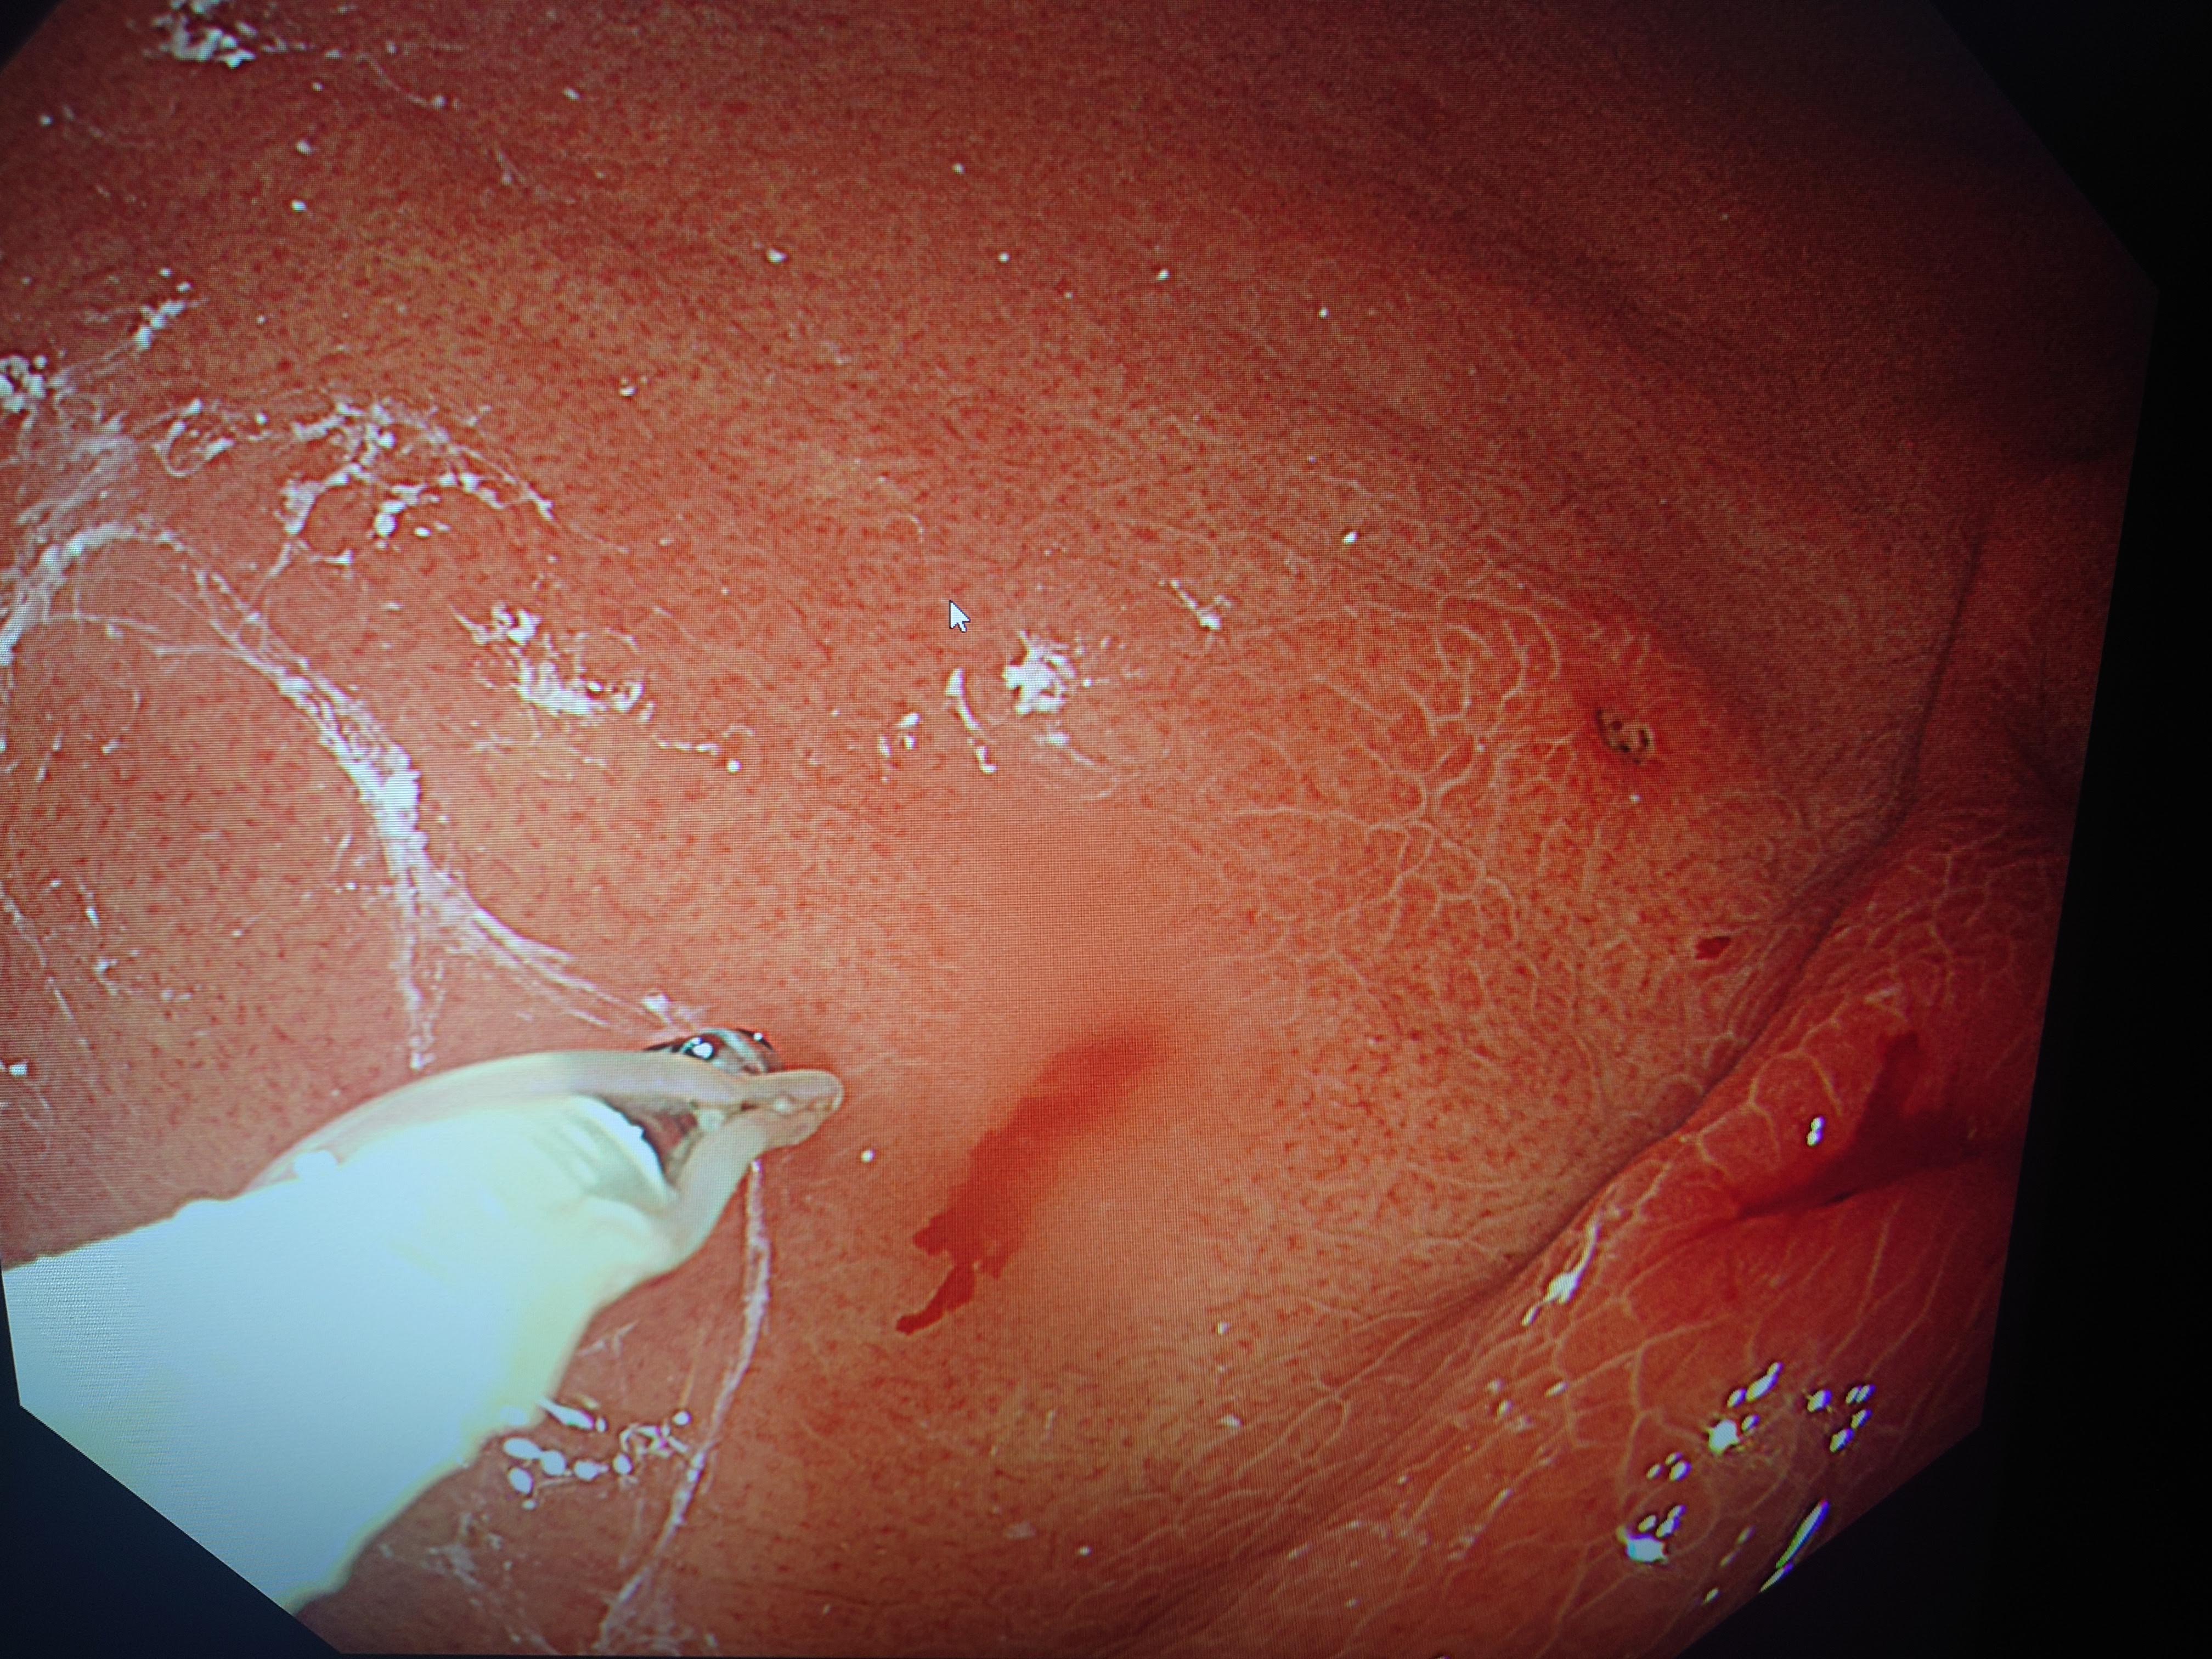

アニサキスが疑われたら可能な限り上部消化管内視鏡検査を施行し、アニサキス中体を確認したら内視鏡的にアニサキス虫体を除去いたします。

アニサキスが実際にいなくても胃のひだの粘膜浮腫、発赤、びらん等アニサキスが食いついた痕跡を認めることがあります。